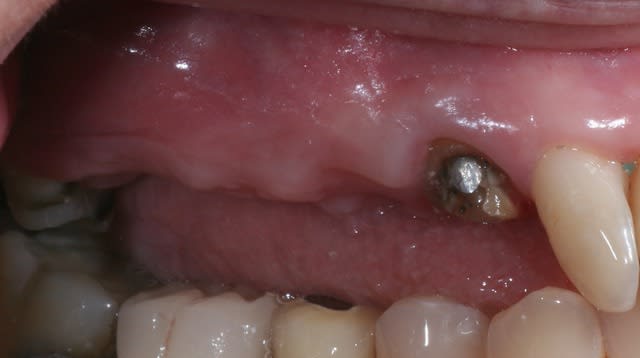

bon finalement 8 mm c'était suffisant.

Img 9010 tehnsv - Eugenol

magnifique mac, tu vas nous faire suivre ce cas step by step.

bon , une question: caractéristiques du fil que tu as utilisé ici ?

sur les conseils d'olivier noah, c'est du prolene 6.0.

Et quel bistouri circulaire as-tu utilisé?

ceux conseillés par vava en 6 et en 8 mm, les mêmes chez astra c'est 12 euros pièce et y en a pas en 8mm.